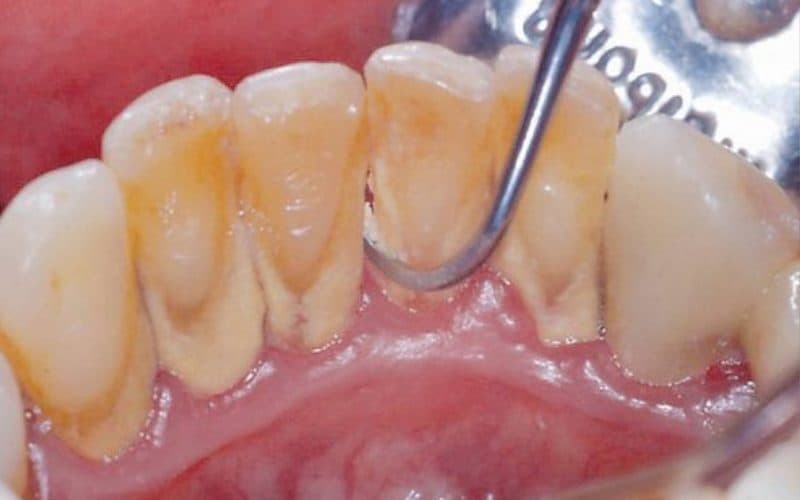

Hình ảnh cao răng

Cao răng thường có màu vàng nhạt hoặc nâu, đôi khi có thể chuyển sang màu đen nếu không được loại bỏ trong thời gian dài. Vị trí thường gặp nhất của cao răng là mặt trong của răng dưới phía trước và mặt ngoài của răng hàm trên, do đây là những vùng gần với các tuyến nước bọt chính.